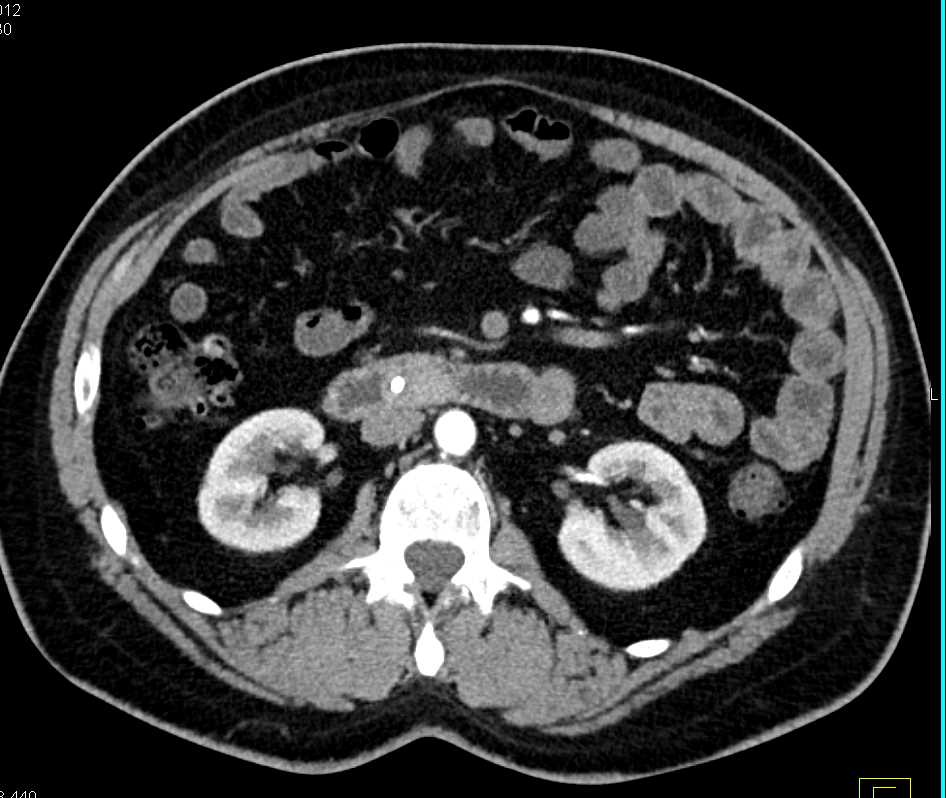

Duodenal Carcinoma in 3D